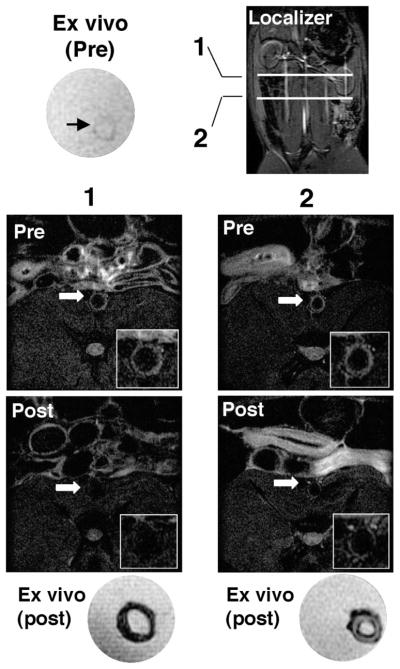

Figure 5.

MRI validated ex vivo the T2 signal reduction effect of MION-47 administration. Before MION-47 injection, the ex vivo atherosclerotic wall showed high T2-SI (top left; ex vivo, pre). The image localizer indicates levels of slices 1 and 2 (bottom). Both in vivo and ex vivo images of slice 1 exhibited the T2-SI reduction in the whole layer of aortic wall. Slice 2 showed in vivo and ex vivo T2-SI reduction in the intimal layer close to the luminal surface.